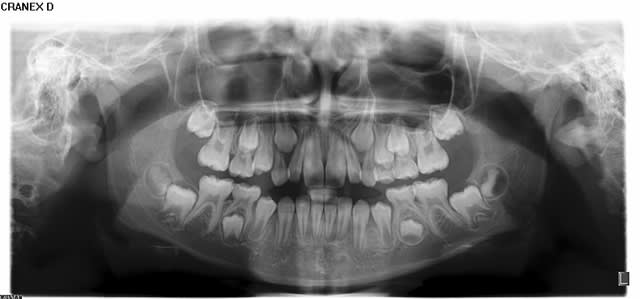

Au niveau dentaire, on observe un taurodontisme (voir molaires sur panoramique).

Il faut regarder les 6 du haut, surtout la 26. En bas, les dents sont nécrosées, le développement s'est arrêté.

L'enfant a 9 ans : compare les molaires du haut avec les pano d'enfants du même age ci-dessous.